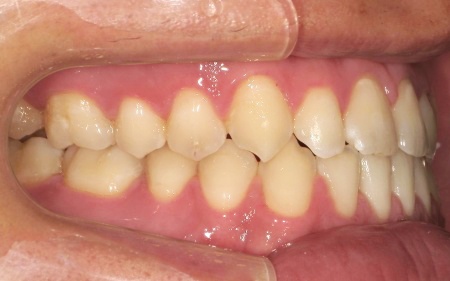

20代男性 受け口のように見える切端咬合をセラミックブラケットによる矯正治療で改善した症例

拝見したところ、上下前歯の先端同士が触れ合う「切端咬合(せったんこうごう)」の状態でした。

通常は上前歯が下前歯をわずかに覆うように重なりますが、患者様の場合は上下前歯の先端がほぼ同じ高さで噛み合っているため、受け口のような印象がみられました。

また、上下前歯の接触により下顎を前に出しにくく、後ろへ押し込まれやすい咬み合わせとなっています。